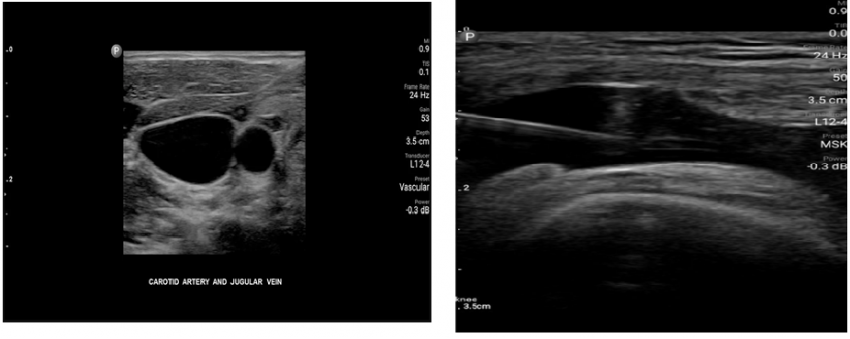

Here are some clinical images from which you can evaluate the quality of visualization and the interface of the program.

The functionality of Ramzed linear transducer software includes presets for thyroid and breast examinations, programs for carotid arteries and peripheral vascular examinations, as well as presets for small organs and superficially located structures.

As for the Ramzed convex probe, there are usually default presets for wide abdominal examinations, prostate examinations, gynecological and obstetrical programs.

The clinical calculation package is available only for superficial obstetrical examinations (not for specialized examinations). As for the other programs, the usual calculations to measure the distance, area and volume of the structures are laid there.